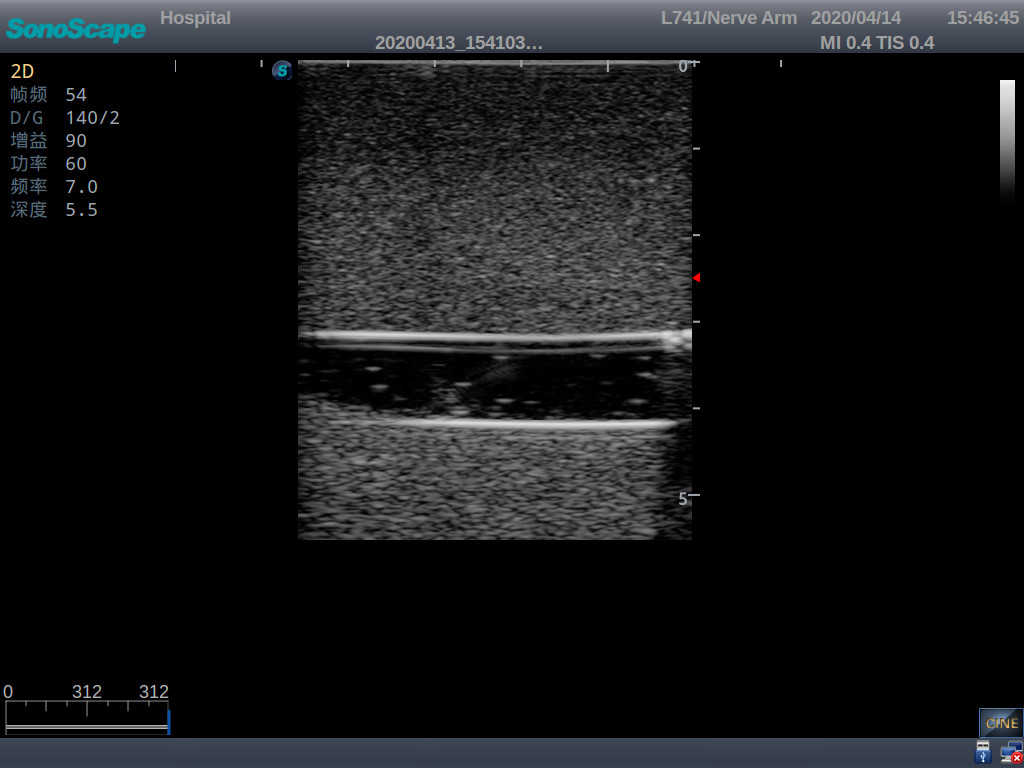

2)   It can be used by real ultrasound machines

3)   Clear and real images of the tissues and organs (basilic vein and superior vena cava)